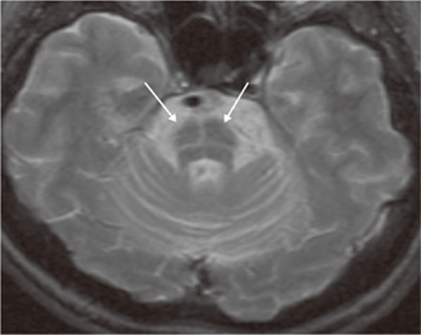

Multiple system atrophy (MSA) is an entity that comprises autonomic failure (OH or a neurogenic bladder) and either parkinsonism (MSA-p) or a cerebellar syndrome (MSA-c). MSA-p is the more common form; the parkinsonism is atypical in that it is usually unassociated with significant tremor or response to levodopa. Symptomatic OH within 1 year of onset of parkinsonism predicts eventual development of MSA-p in 75% of patients. Although autonomic abnormalities are common in advanced Parkinson’s disease (Chap. 30), the severity and distribution of autonomic failure is more severe and more generalized in MSA. Brain MRI is a useful diagnostic adjunct; in MSA-p, iron deposition in the striatum may be evident as T2 hypointensity, and in MSA-c cerebellar atrophy is present with a characteristic T2 hyperintense signal (“hot cross buns sign”) in the pons (Fig. 33-2). Cardiac postganglionic adrenergic innervation, measured by uptake of fluorodopamine on positron emission tomography, is markedly impaired in the dysautonomia of Parkinson’s disease but is usually normal in MSA.

FIGURE 33-2

Multiple system atrophy, cerebellar type (MSA-c). Axial T2-weighted MRI at the level of the pons shows a characteristic hyperintense signal, the “hot cross buns” sign.